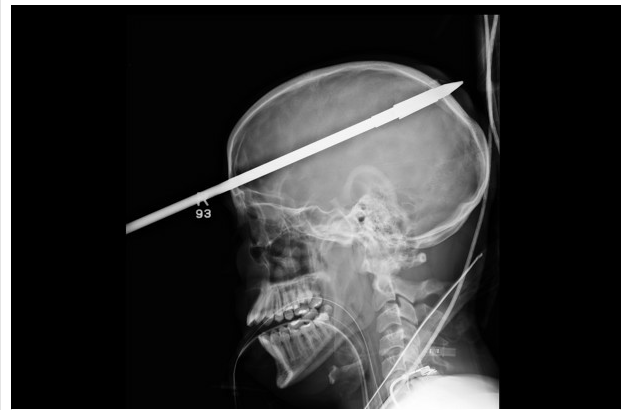

June 19, 2012 Lucky miss via Fla. doctors remove spear from teen’s skull, say it missed all main blood vessels in his brain – The Washington Post. share the love: Email a link to a friend (Opens in new window) Email Share on Facebook (Opens in new window) Facebook Share on Tumblr (Opens in new window) Tumblr Share on X (Opens in new window) X Share on Pinterest (Opens in new window) Pinterest Like Loading... Related